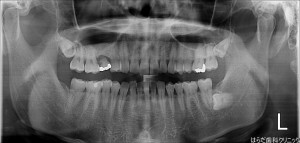

本日は杉村先生による右上5番のインプラントオペが行われました。

オペを行う前と後にはレントゲン写真を撮り状態のチェック、確認を致しますので何か心配な事、気になる事にも迅速に対応致します。

本日は1本の埋入でしたので約1時間で終了しました。